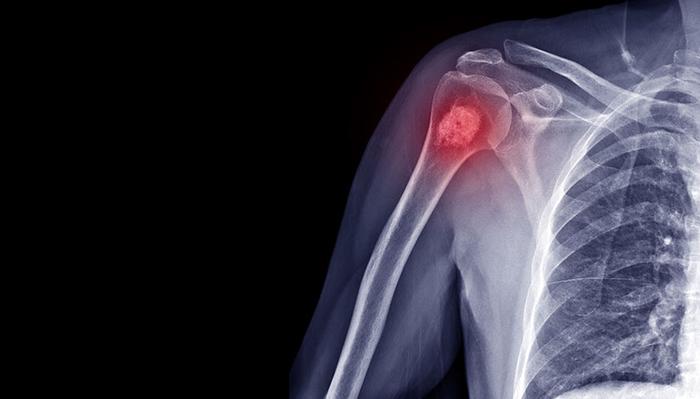

Рак Костей Симптомы И Проявление Фото